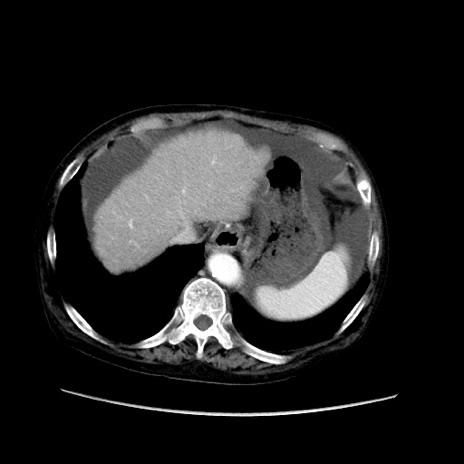

症例31(横断像)

【症例】80歳代 女性

【主訴】腹部膨満感

【現病歴】他院にて肝硬変にてフォロー中。1週間前から便秘、腹部膨満感、臍部腫瘤あり受診となる。

【既往歴】肝硬変

【身体所見】腹部膨隆あり、皮膚変化なし、疼痛なし。

【データ】WBC 4600、CRP 0.25